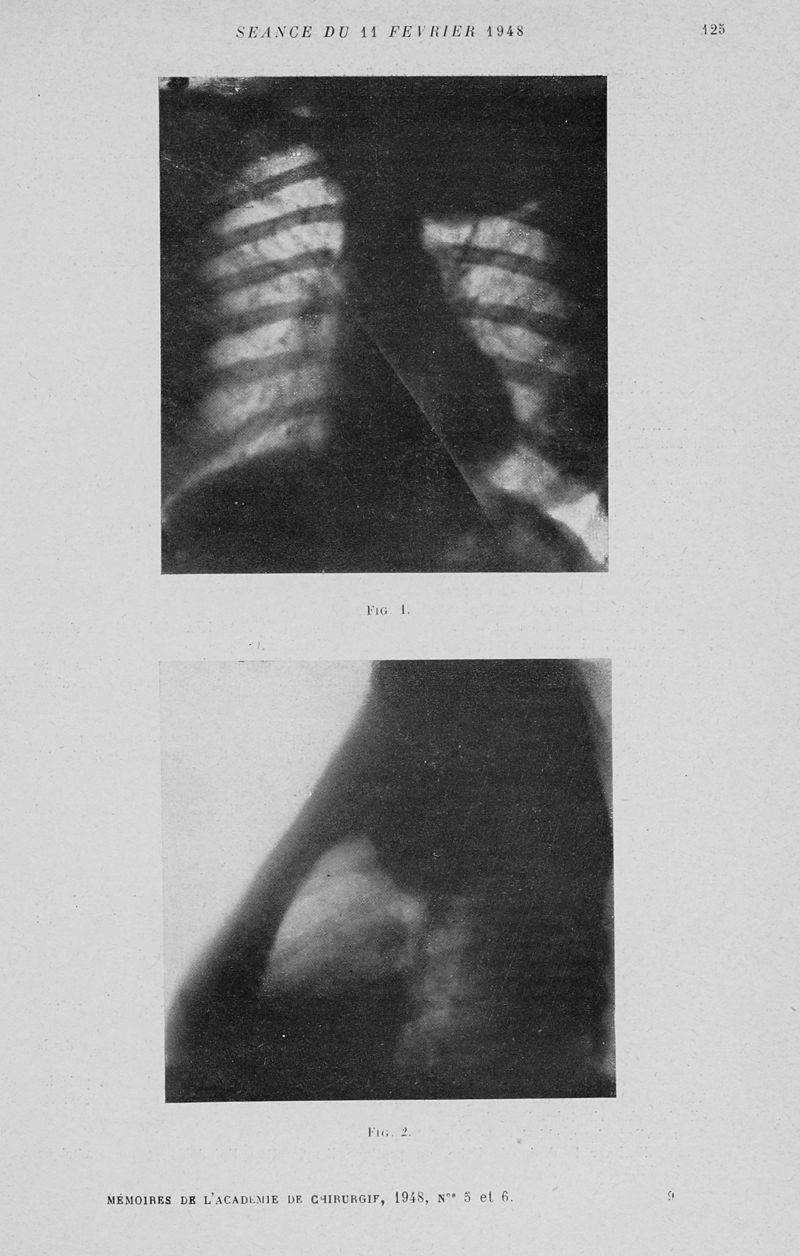

Mémoires de l'académie de chirurgie

Tome 74, 1948. - Paris : Masson, 1948.